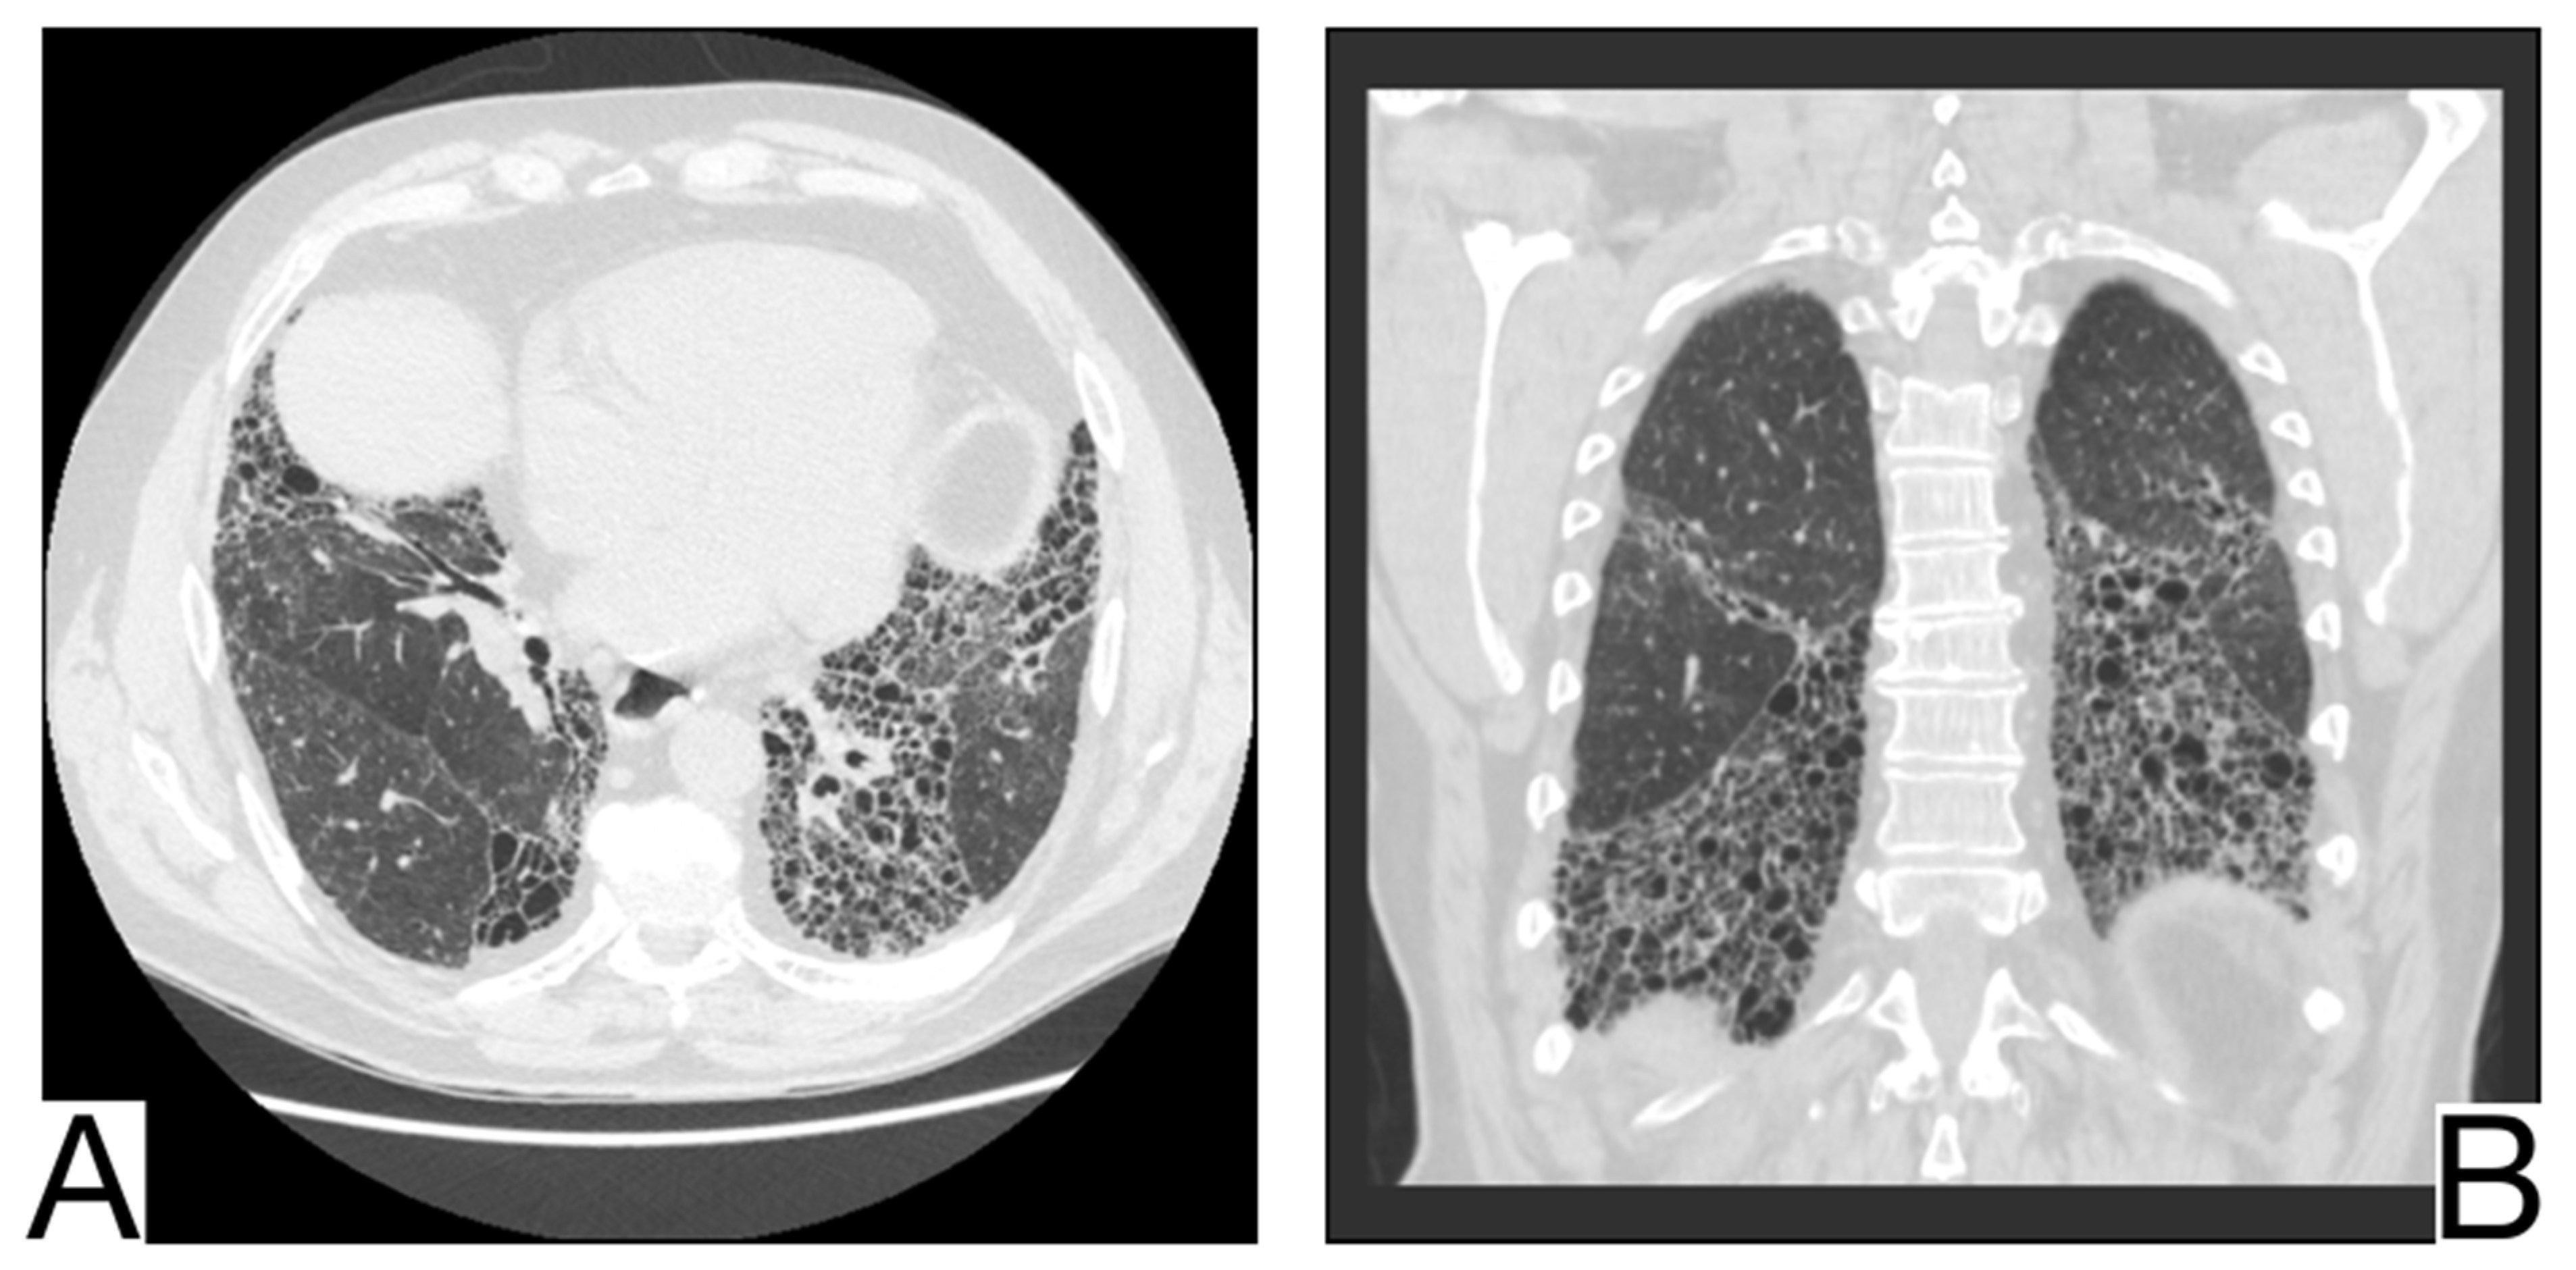

10.10. Pulmonary Alveolar Proteinosis

9. Diagnostic Imaging